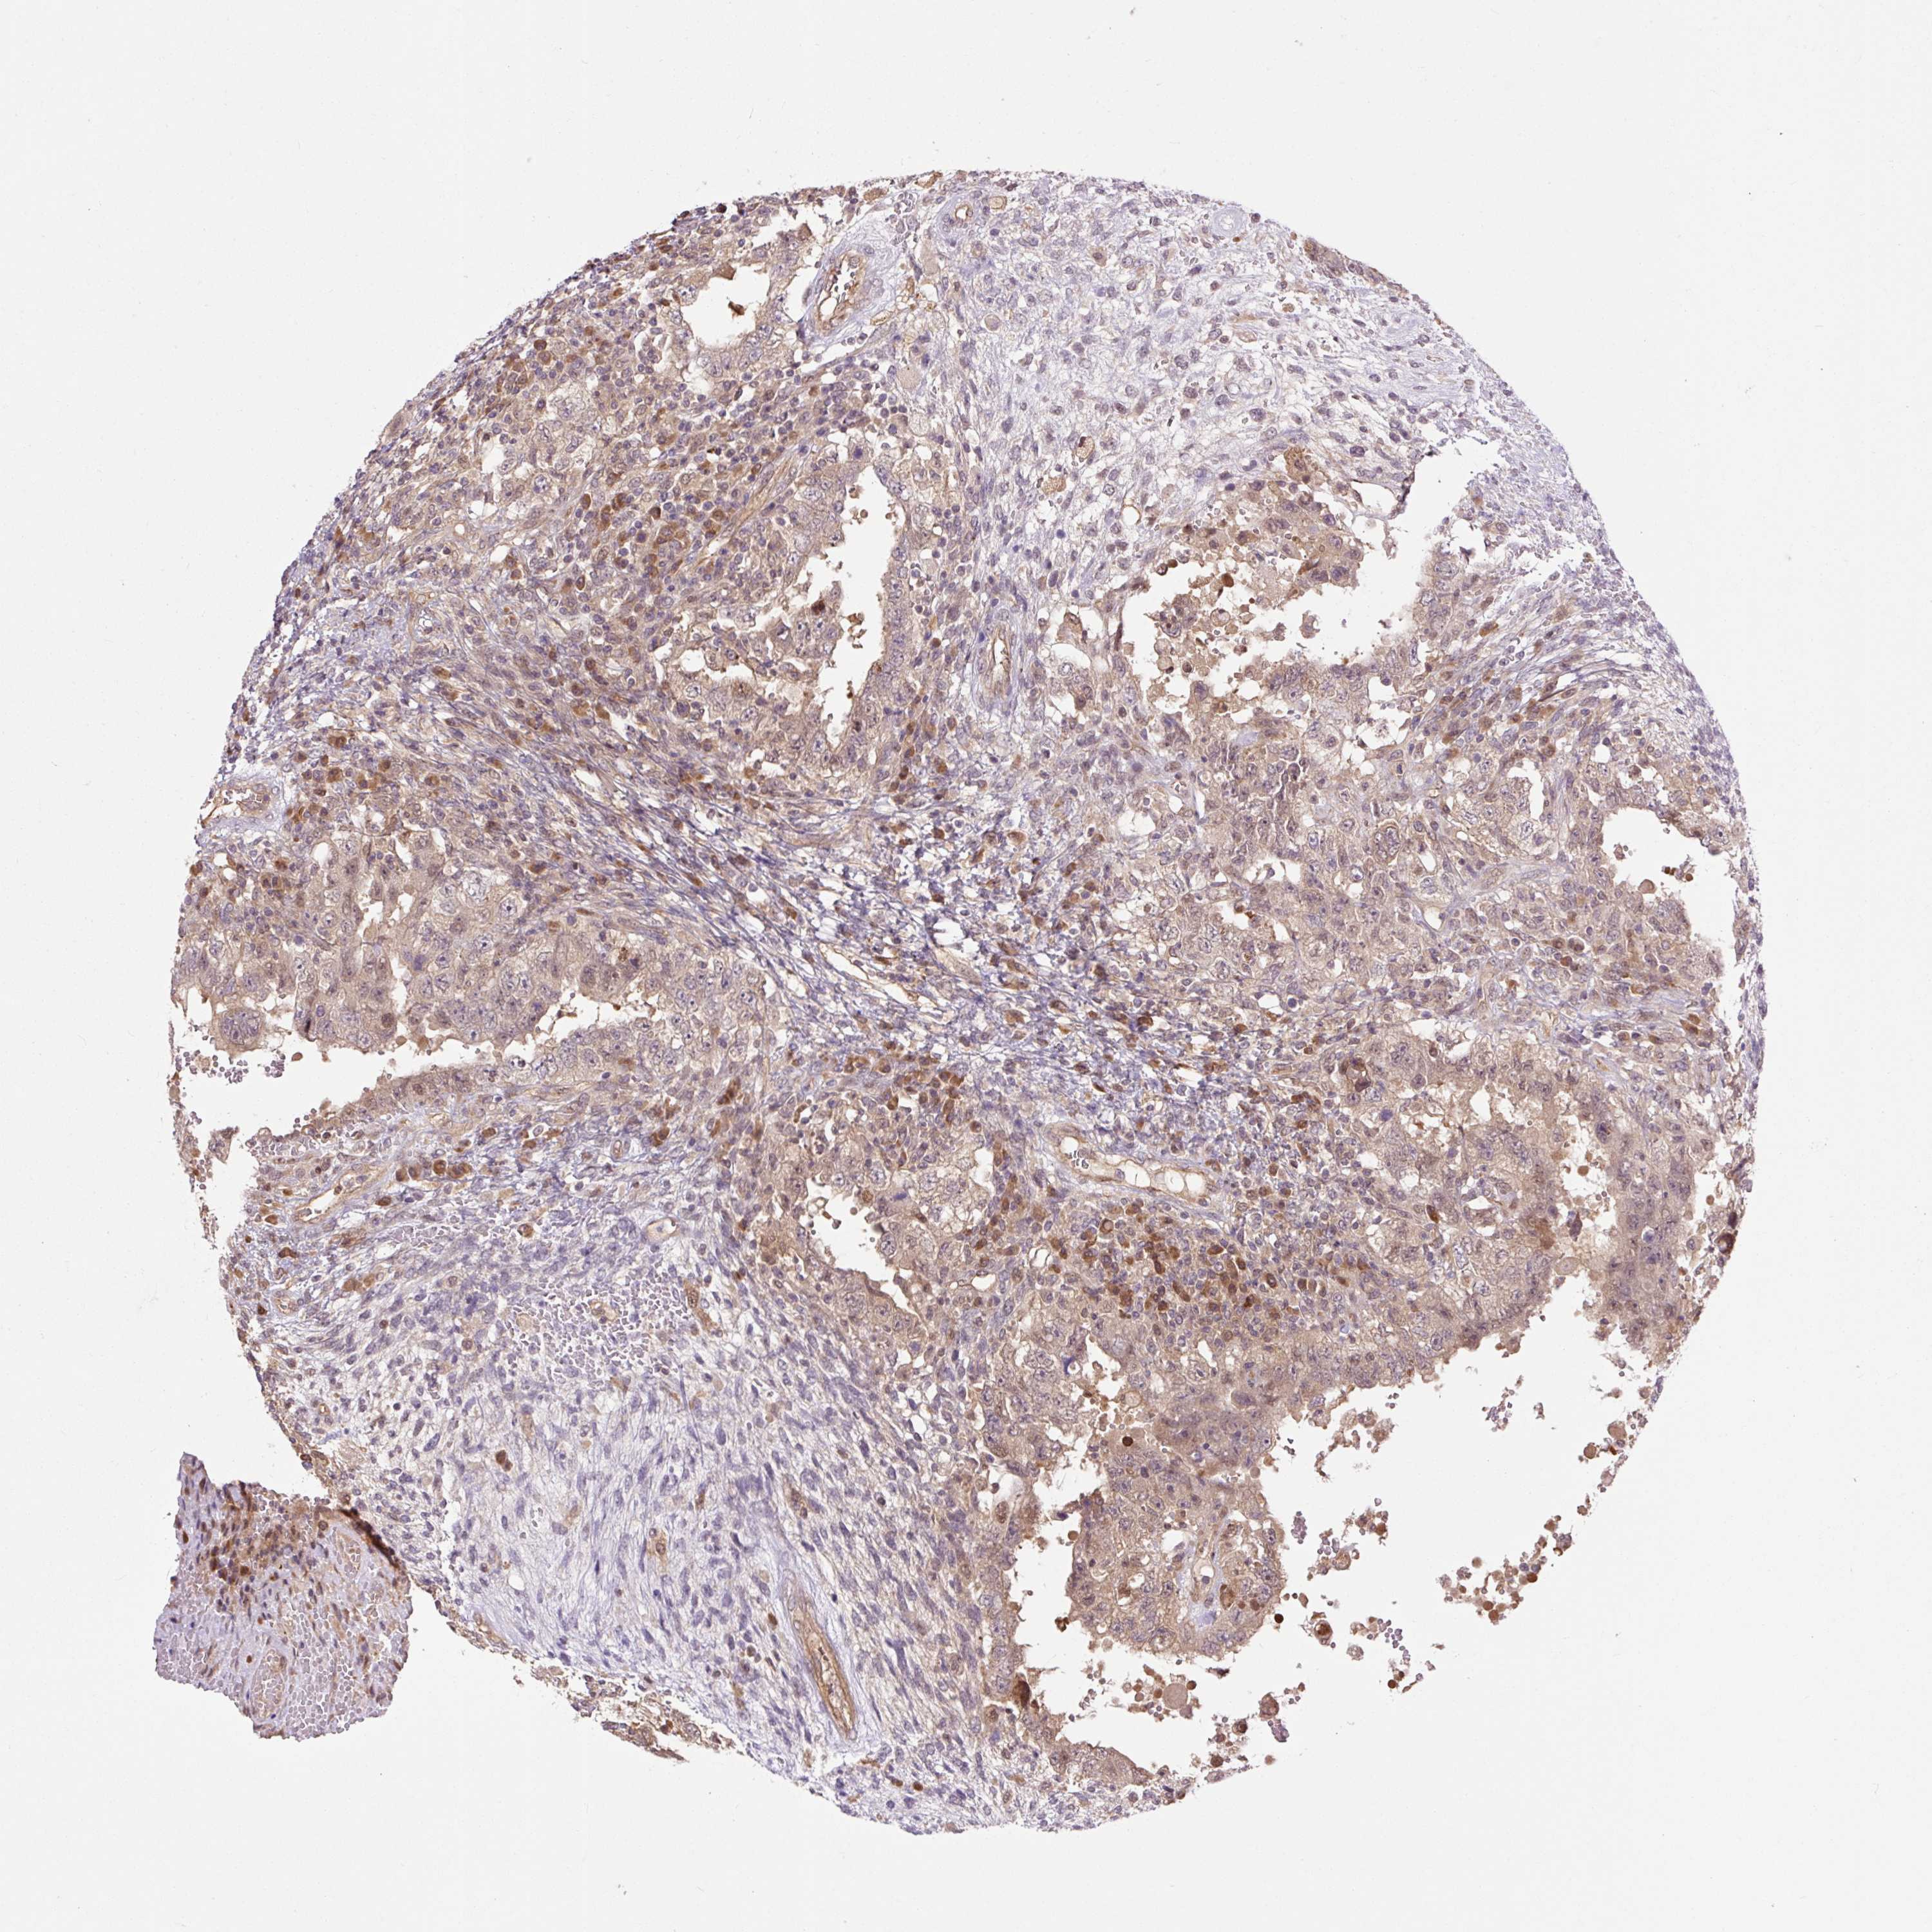

TESTIS CANCER - Protein expressioni

A mouse-over function shows sample information and annotation data. Click on an image to view it in a full screen mode. Samples can be filtered based on level of antibody staining by selecting one or several of the following categories: high, medium, low and not detected. The assay and annotation is described here.

Note that samples used for immunohistochemistry by the Human Protein Atlas do not correspond to samples in the TCGA dataset.

Antibody stainingi

Antibody staining in the annotated cell types in the current human tissue is reported as not detected, low, medium, or high, based on conventional immunohistochemistry profiling in selected tissues. This score is based on the combination of the staining intensity and fraction of stained cells.

Each image is clickable and will lead to virtual microscopy that enables deeper exploration of all samples and also displays staining intensity scores, fraction scores and subcellular localization as well as patient and tissue information for each sample.

Antibody HPA039437

Antibody HPA073929

Antibody CAB008364

Staining

High

Medium

Low

Not detected

Intensity

Strong

Moderate

Weak

Negative

Quantity

>75%

75%-25%

<25%

None

Location

Nuclear

Cytoplasmic/membranous

Cytoplasmic/membranous,nuclear

Carcinoma, Embryonal, NOS

Seminoma, NOS